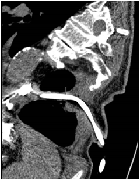

Cerebral Edema Treated Successfully after Liver Transplant in a Patient with Acute Iron Toxicity

Fariha Hussain, Tuba Rashid Khan, Pallav Bhattarai*, Lakshmi Raman